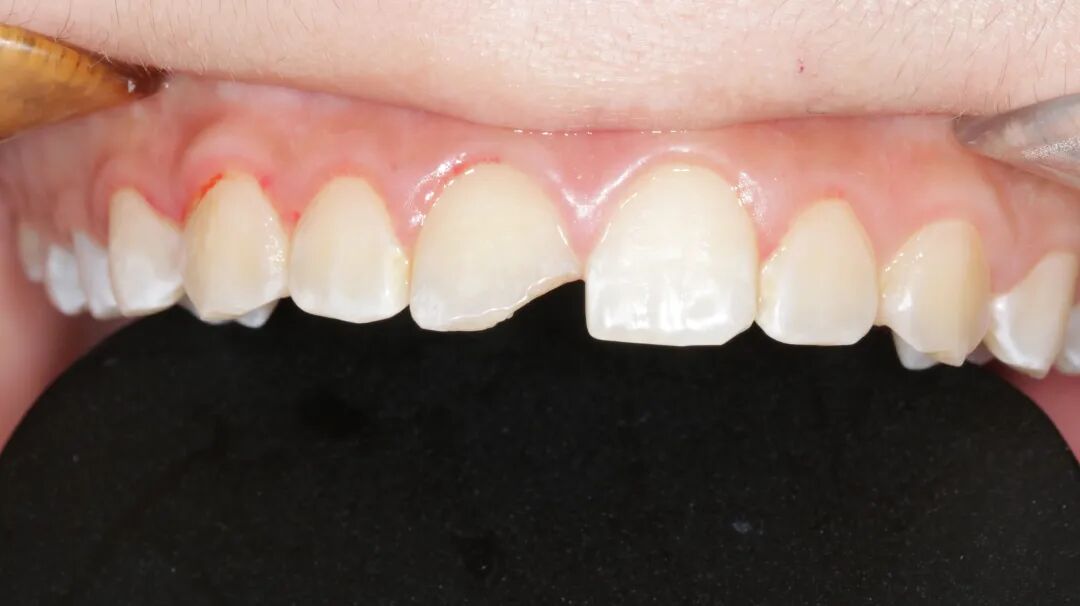

上颌中切牙瓷贴面美学修复

性别:女     年龄21岁

主诉:前牙氟斑牙影响美观

现病史:病人因从小有高氟地区生活史,导致全口氟斑牙,现因前牙区氟斑牙呈黄褐色影响美观,要求处理

检查:牙龈无红肿,口内卫生良好

治疗方案:铸瓷贴面美学修复